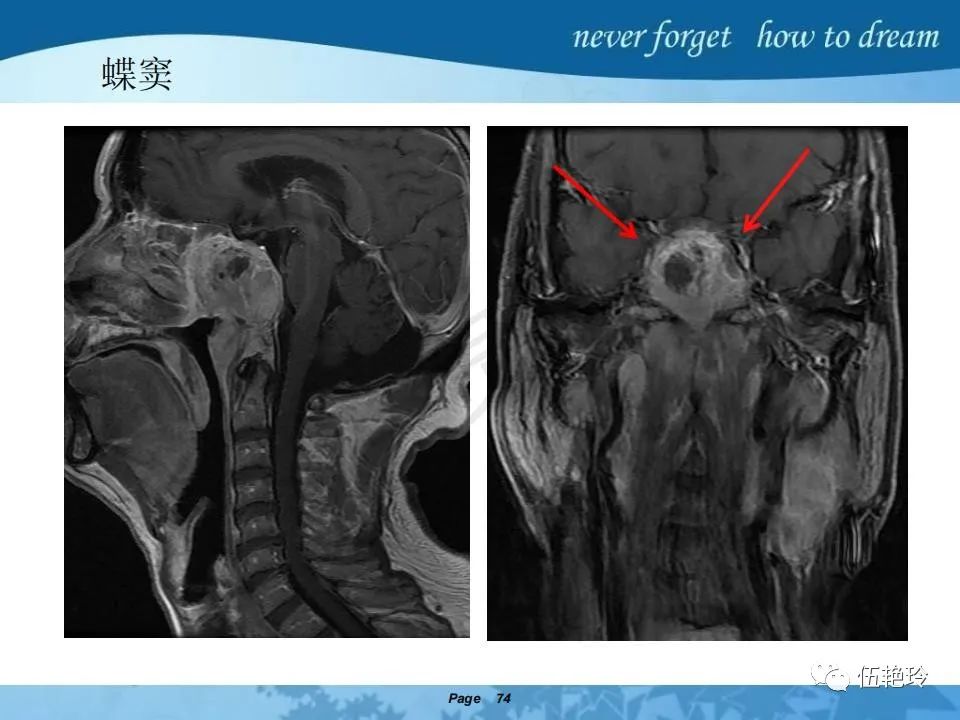

海绵窦区的解剖结构与鼻咽癌侵犯

2.31 向上颅内:①鼻咽顶壁→破裂孔(岩尖、斜坡)→蝶窦、海绵窦;②鼻咽顶壁→蝶骨基底部→蝶窦、海绵窦;③鼻咽侧壁→茎突前间隙→蝶骨大翼(卵圆孔)→海绵窦;④鼻咽侧壁→茎突前间隙→翼腭窝→ 颞下窝;⑤鼻咽前壁→鼻腔→翼突、翼腭窝→眶下裂→眶尖→海绵窦;⑥鼻咽前壁→鼻腔→上颌窦、筛窦;